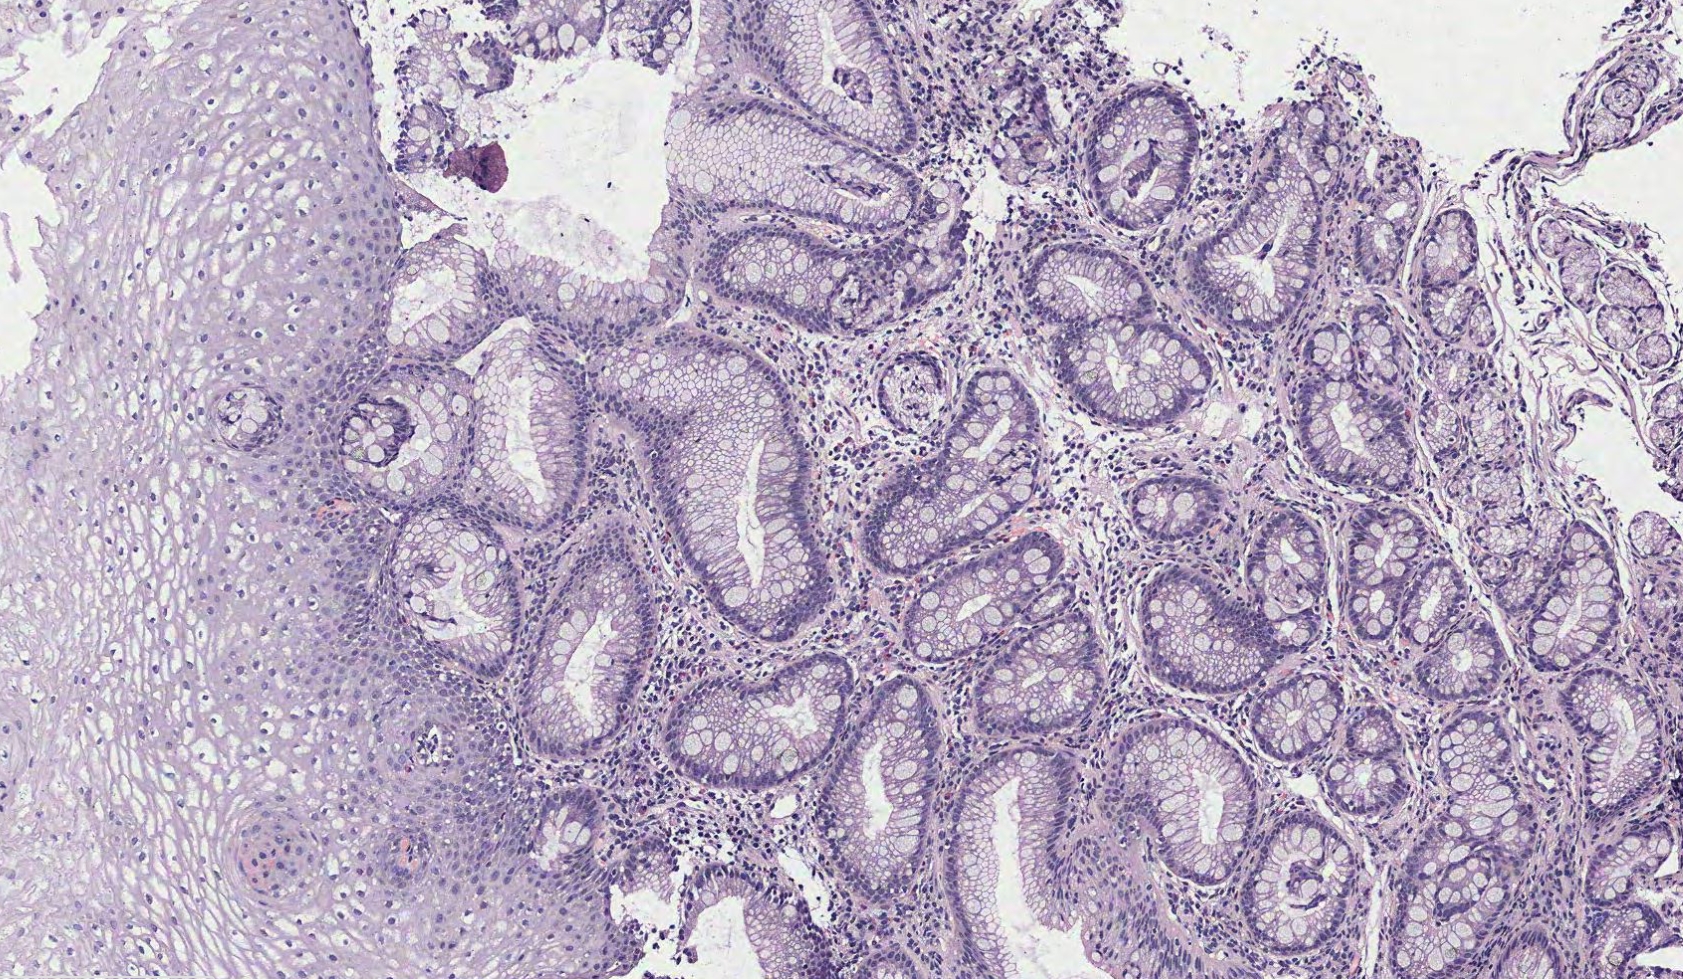

Общая патанатомия

Общая патанатомия 131 фото